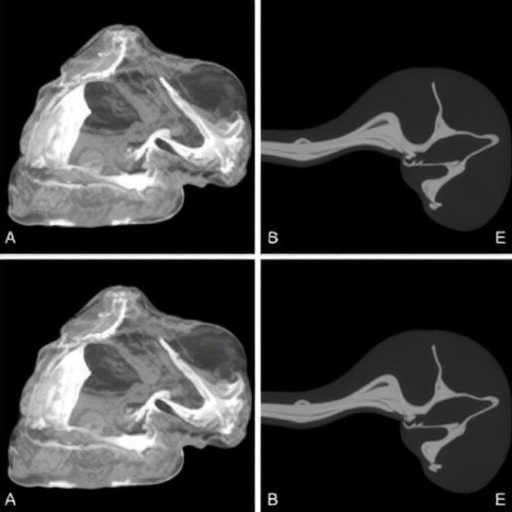

The case reported by the authors details a young patient presenting with proboscis lateralis diagnosed in the early stages of life. Upon clinical examination, distinct features were noted that confirmed the diagnosis of congenital nostril hypoplasia. This aberration, characterized by underdeveloped nasal passages, poses significant respiratory challenges and risks of severe complications if not managed promptly. The researchers meticulously outline the diagnostic processes involved, including advanced imaging techniques such as MRI and CT scans, which are essential in visualizing the underlying abnormalities associated with this condition.

Furthermore, the occurrence of a trans-ethmoidal meningocele adds yet another layer of complexity to the patient’s condition. This particular type of meningocele involves the herniation of the meninges—protective coverings of the brain—through a defect in the ethmoid bone. This condition is relatively rare, and its association with proboscis lateralis underscores the need for a multidisciplinary approach to patient care. The authors share their insights on the potential pitfalls in diagnosing such intertwined anomalies, emphasizing the necessity for collaboration among pediatricians, neurologists, and surgical teams.